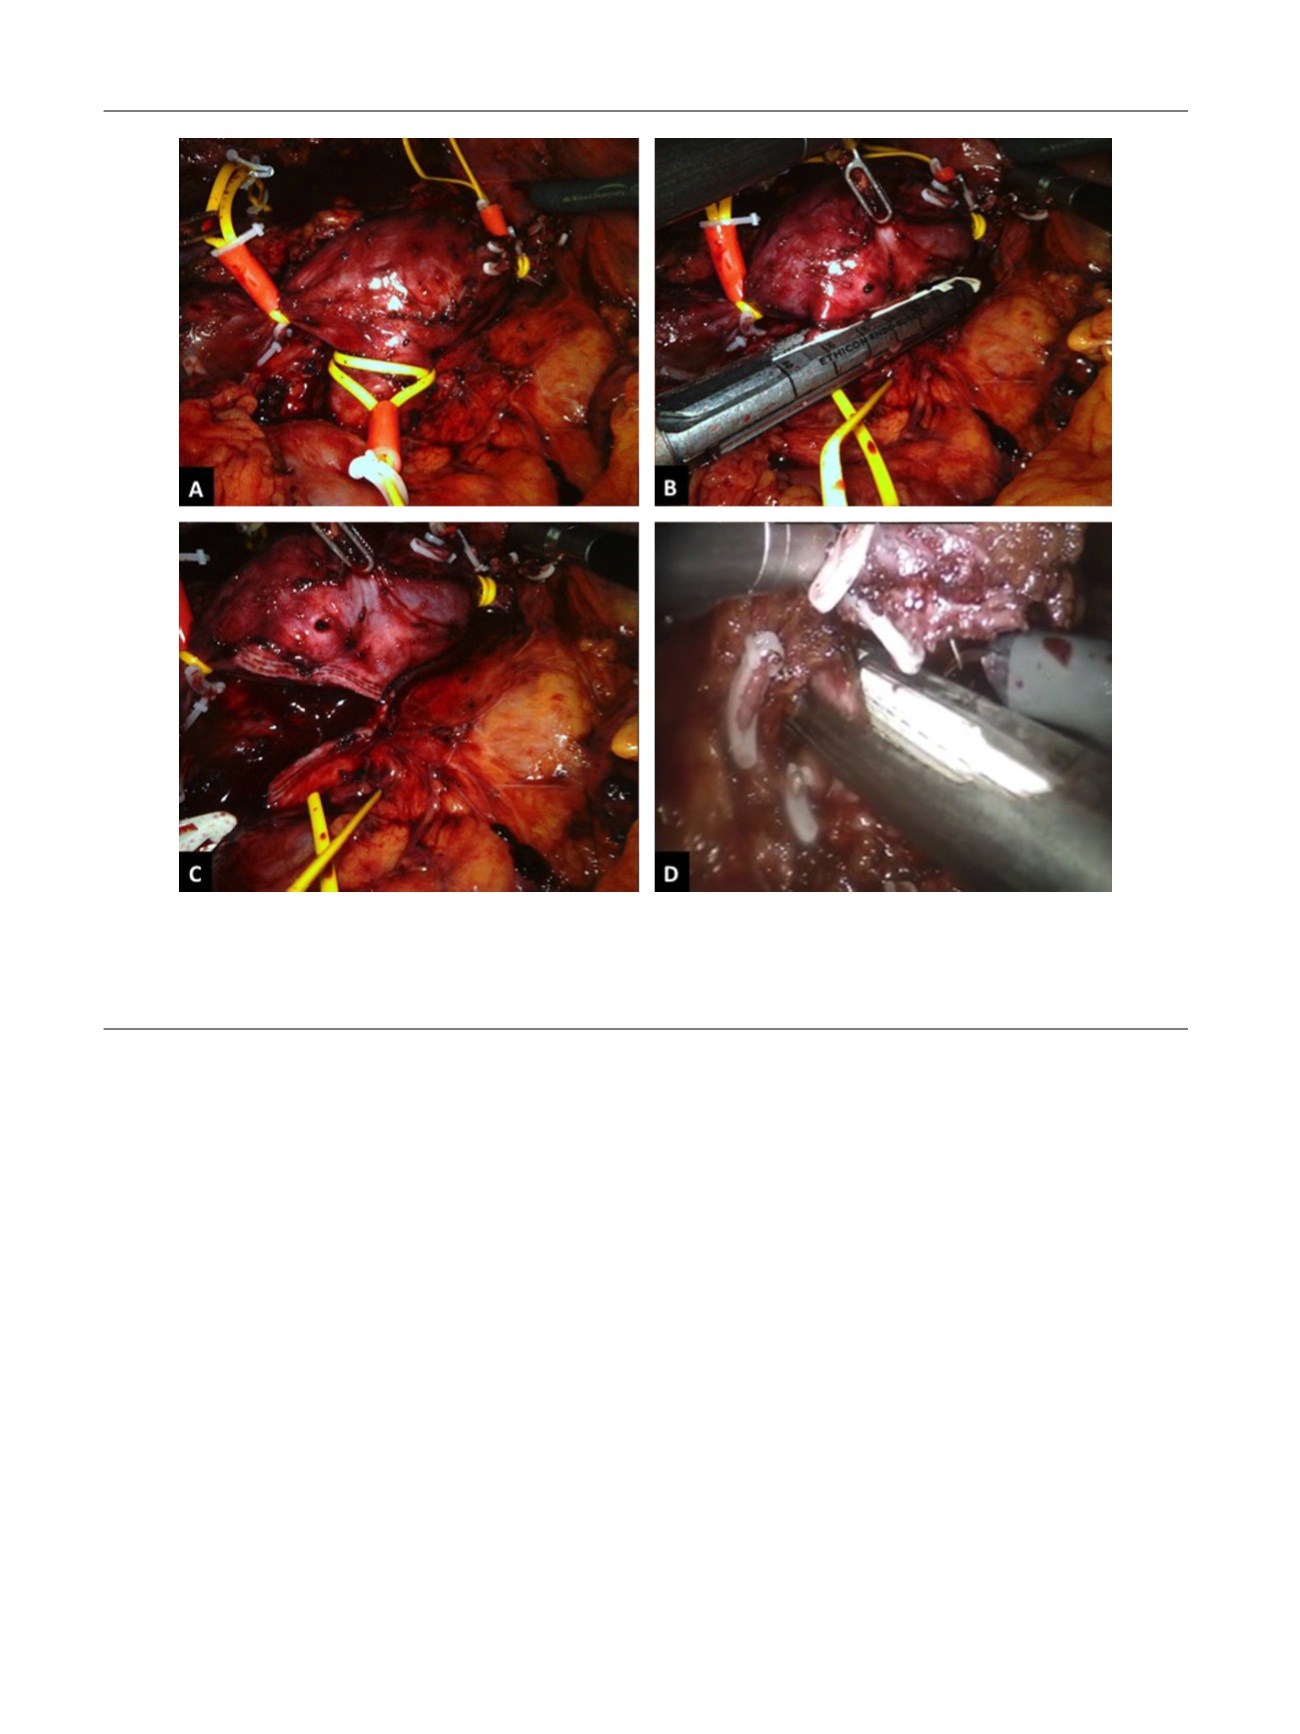

Fig. 4 – Left-sided caval thrombectomy. (a) The infrarenal inferior vena cava (IVC), suprarenal IVC, left and right renal veins are encircled with a

double-loop tourniquet and secured with a Hem-o-lok clip. Then the right renal artery and right renal vein are controlled using individual bull-dog

clamps. (Note: In this operative picture, the patient had a solitary kidney. The previous kidney was emergently removed during a previous motor

vehicle accident). (b, c) The thrombus-bearing left renal veins is transected with an Endo GIA stapler after have already undergone preoperative

angioembolization. (d) The left renal artery is ligated following patient repositioning.